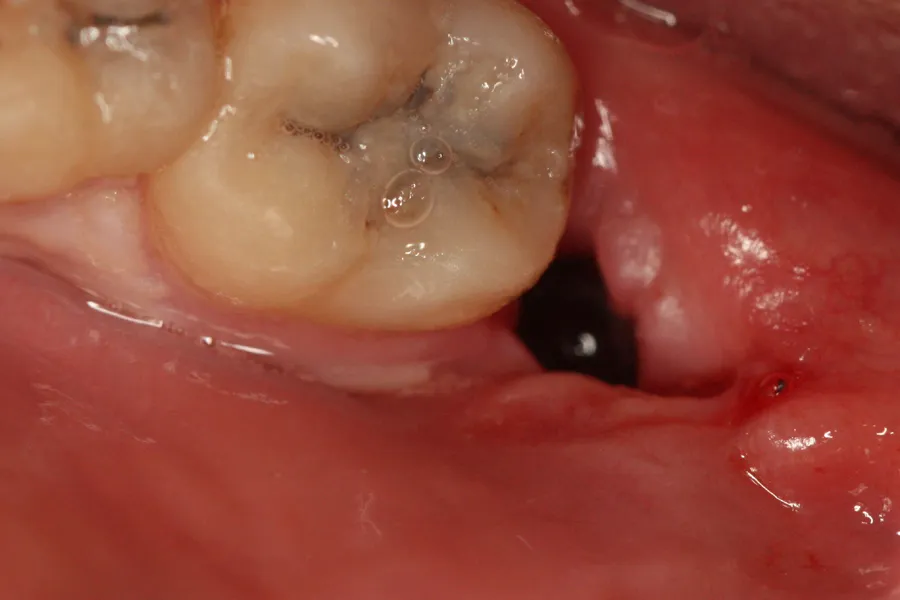

Jak wygląda prawidłowy włóknik? Charakterystyka zdrowej rany

Kolor i konsystencja: czego powinieneś się spodziewać, patrząc w lustro?

Prawidłowy włóknik w ranie po ekstrakcji zęba ma zazwyczaj kolor biały, biało-żółty, a czasem nawet lekko szarawy. Nie powinien być jaskrawo żółty czy zielony, co mogłoby wskazywać na ropę. Jego konsystencja jest jednolita wygląda jak szczelnie przylegający nalot lub delikatna błonka, która pokrywa dno rany. Nie powinien być luźny, łatwo dający się usunąć ani rozpadać się. Wyobraź sobie, że to taki naturalny, miękki opatrunek, który idealnie dopasowuje się do kształtu zębodołu.

Od czerwonego skrzepu do białego nalotu: wizualna podróż przez etapy gojenia

Obserwując ranę, zauważysz naturalną progresję. Bezpośrednio po zabiegu rana będzie wypełniona intensywnie czerwonym skrzepem krwi. Po kilku dniach, gdy skrzep zacznie dojrzewać i na jego powierzchni wytrąci się włóknik, kolor rany zmieni się na jaśniejszy właśnie na ten charakterystyczny białawy lub żółtawy odcień. Ta wizualna transformacja jest zupełnie normalna i świadczy o prawidłowo postępującym procesie gojenia. To nie jest powód do niepokoju, a wręcz przeciwnie znak, że organizm wykonuje swoją pracę.